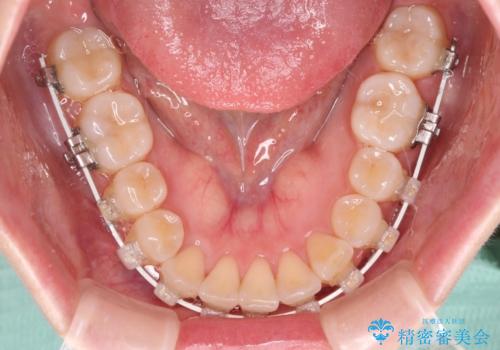

- 上下前歯のデコボコを気にして来院された患者様です。

ワイヤー矯正でもインビザライン矯正でも対応可能でしたが、インビザラインでの自己管理の煩わしさを避けるため、ワイヤー装置にて矯正治療を行うこととしました。

患者様も驚く、僅か10か月での治療終了となりました。

下顎前歯が1歯欠損しているため、上下正中は合わず、左右奥歯の咬み合わせは理想的とはならない仕上がりとなります。